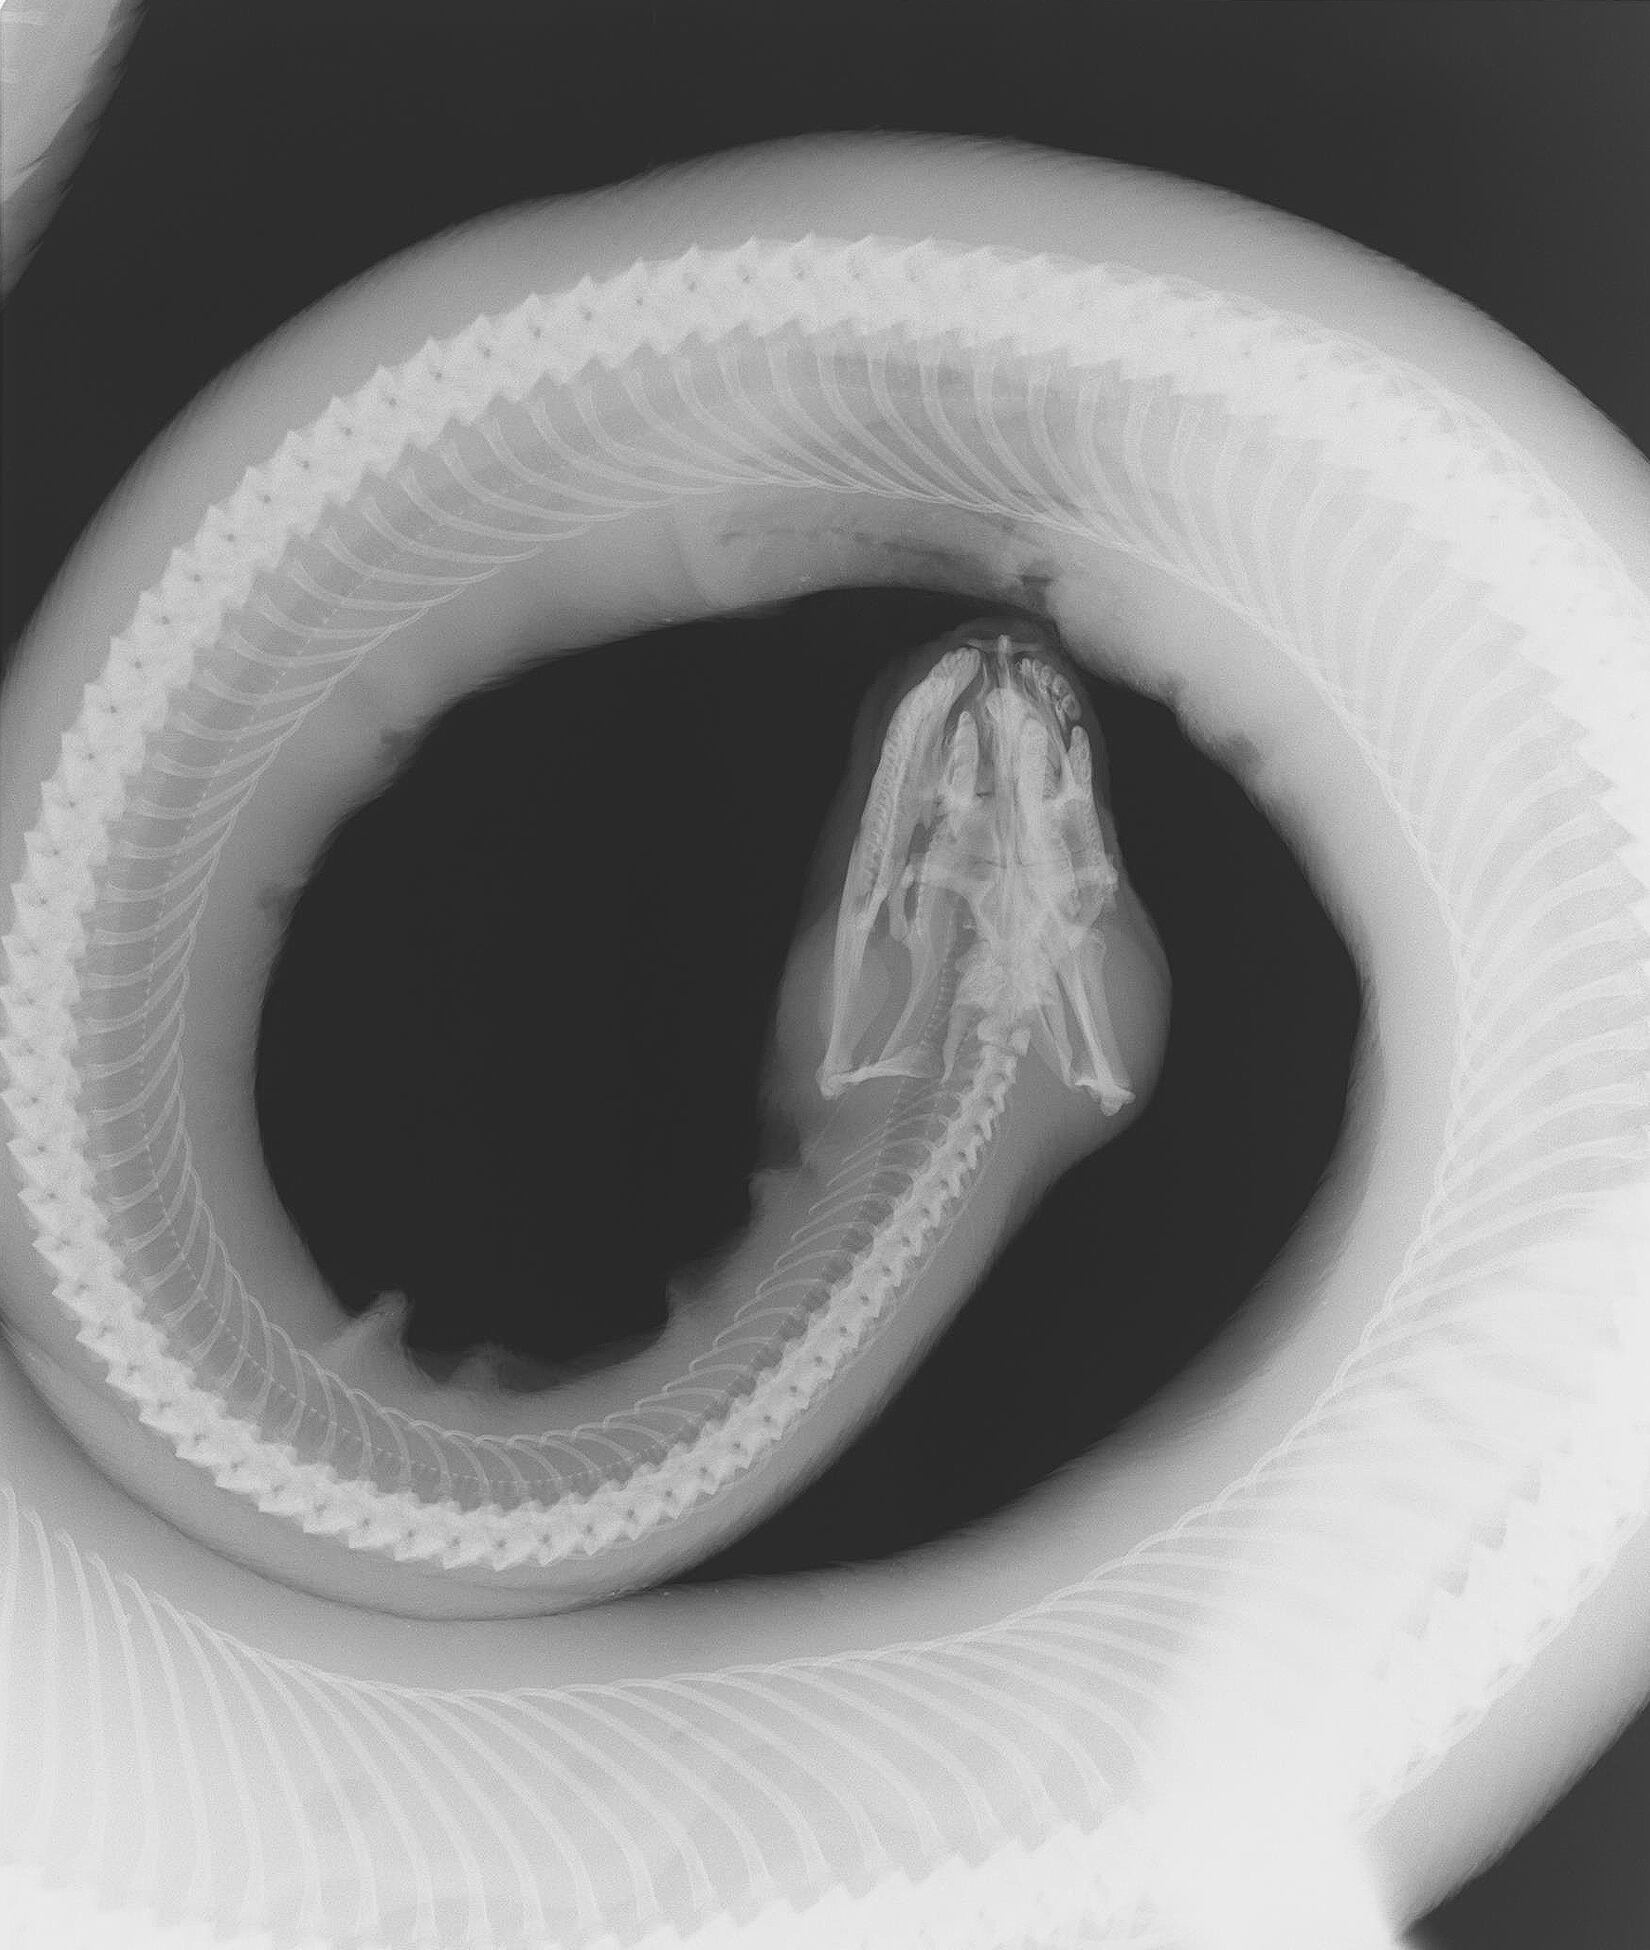

En la clínica veterinaria del Centro de Rescate y Rehabilitación de Vida Silvestre Alturas, ubicada en la Península de Osa, la medicina encontró una forma de dar voz a esa nebulosa con la colección de radiografías El interior de la conservación.

El enfoque de las postales, coloradas en blanco y negro, evitan la crudeza visual, pero no omiten el dolor: evocan el malestar de un pelícano con un anzuelo incrustado en una de sus patas, o uno de los tantos monos fracturados tras caer al asfalto electrocutados.

La radiografía de una boa enroscada, que a simple vista podría parecer serena, oculta una historia de maltrato. Llegó al santuario con heridas de machete, mientras que sus congéneres han aparecido con quemaduras, producto de haberse refugiado en el motor de un automóvil.